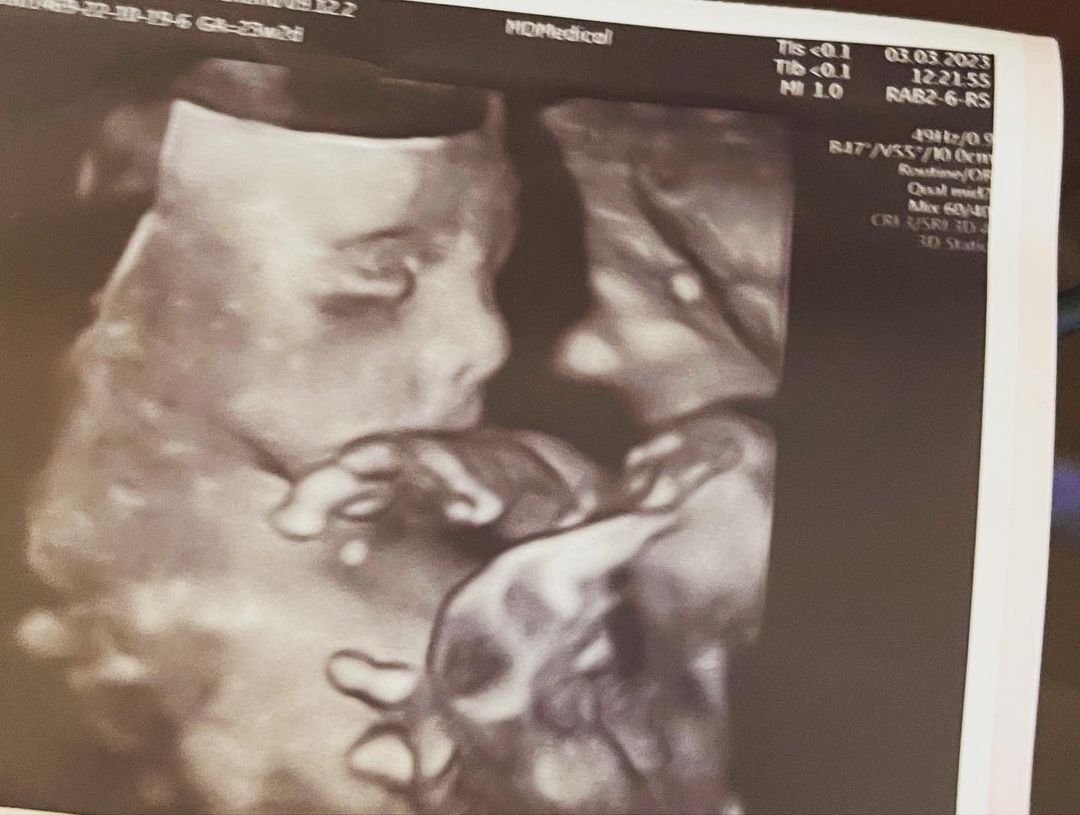

Adriana Simionescu traversează cea mai frumoasă perioadă din viața ei, de când a aflat că va deveni mămică. Fiica lui Adrian Minune a anunțat de curând sexul bebelușului, iar recent a publicat și o ecografie, care redă aproape perfect chipul fetiței sale.

Tânăra și viitorul ei soț au trăit emoții de nedescris în momentul în care au aflat că vor deveni părinți de fetiță. Același lucru li s-a întâmplat și la cea mai recentă ecografie, căci au putut vedea în sfârșit trăsăturile micuței lor: „Astăzi suntem fericiți. Așa suntem de fiecare dată când domnul doctor ne spune că minunea noastră mică este bine!”, a scris Adriana Simionescu pe contul personal de Instagram, în dreptul unei imagini cu ecografia bebelușului său.